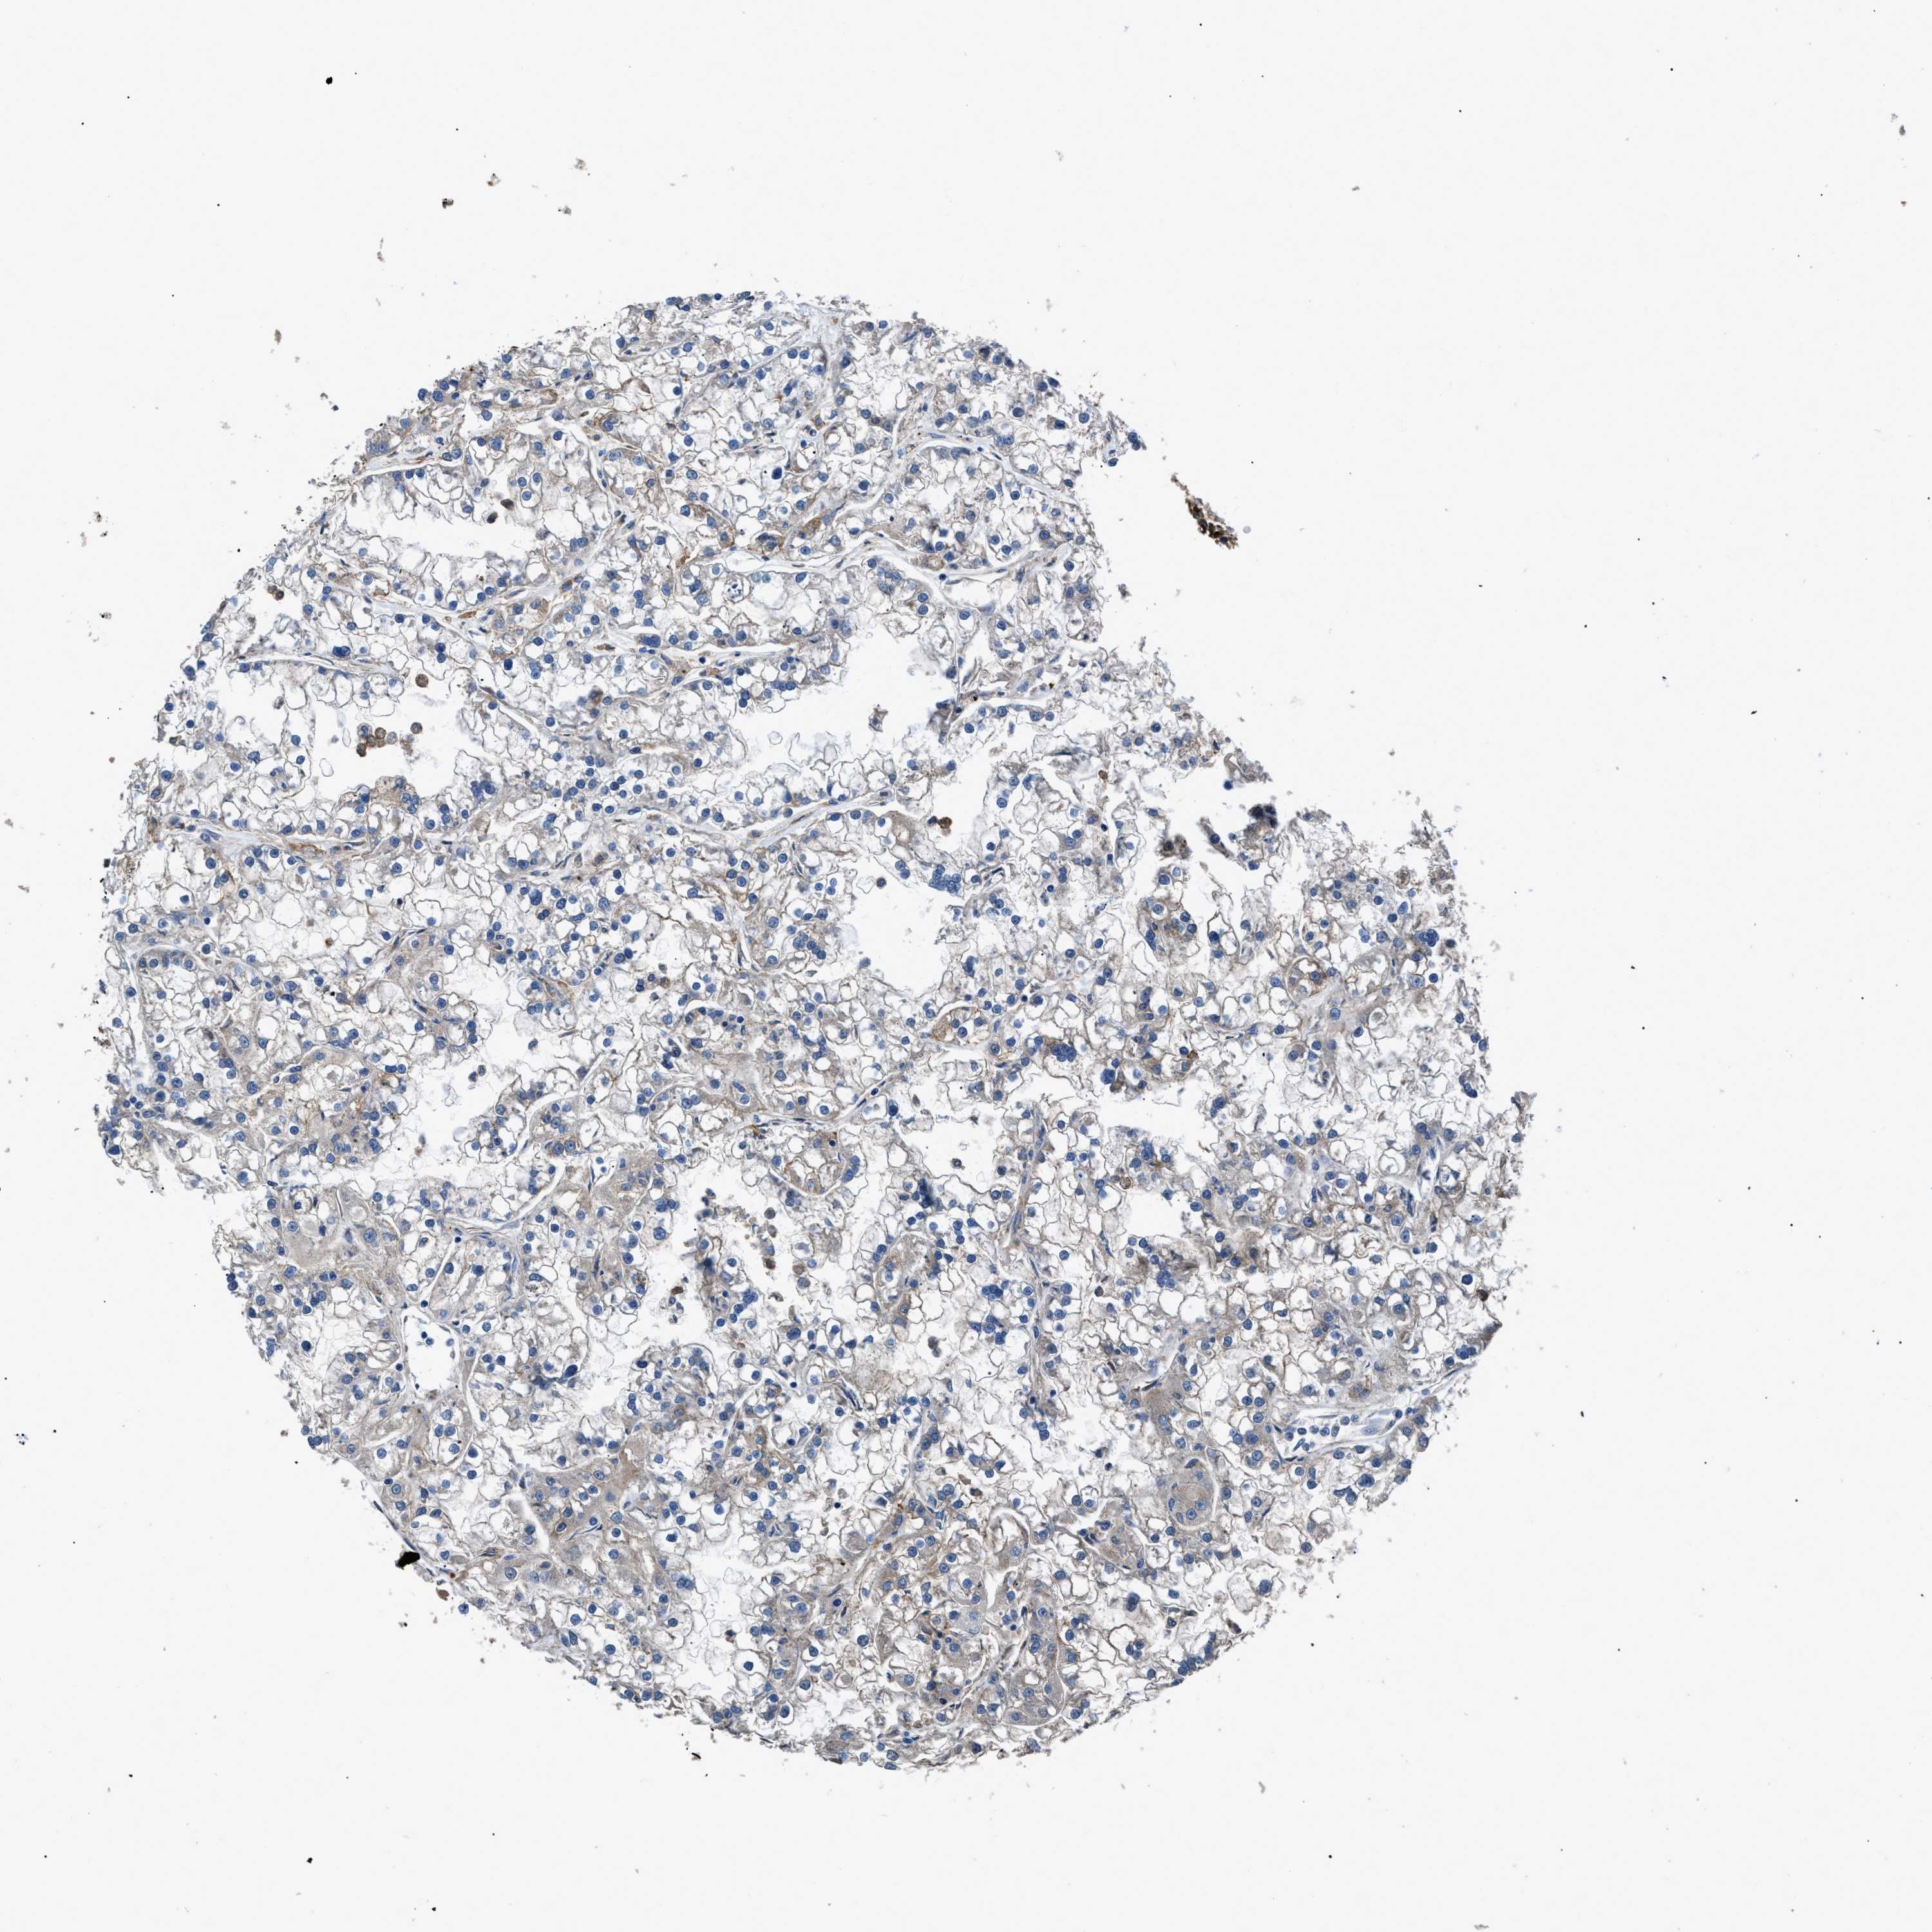

KIDNEY CHROMOPHOBE (TCGA) - Interactive survival scatter ploti

The Survival Scatter plot shows the clinical status (i.e. dead or alive) for all individuals in the patient cohort, based on the same data that underlies the corresponding Kaplan-Meier plots. Patients that are alive at last time for follow-up are shown in blue and patients who have died during the study are shown in red.

The x-axis shows the expression levels (FPKM) of the investigated gene in the tumor tissue at the time of diagnosis. The y-axis shows the follow-up time after diagnosis (years). Both axes are complimented with kernel density curves demonstrating the data density over the axes. The top density plot shows the expression levels (FPKM) distribution among dead (red) and alive patients (blue). The right density plot shows the data density of the survived years of dead patients with high and low expression levels respectively, stratified using the cutoff indicated by the vertical dashed line through the Survival Scatter plot. This cutoff is automatically defined based on the FPKM cutoff that minimizes the p-score. The cutoff can be changed by dragging the vertical line or by entering a cutoff value in the square labeled "Current cut-off".

Under the Survival Scatter plot the p-score landscape (black curve; left axis) is shown together with dead median separation (red curve; right axis). Dead median separation is the difference in median mRNA expression between patients who have died with high and low expression, respectively. It is calculated as follows: median FPKM expression of dead patients with high expression - median FPKM expression of dead patients with low expression. This is intended to aid the user in visually exploring custom cutoffs and the associated p-scores and dead median separation.

Individual patient data is displayed and can be filtered by clicking on one or more of the category buttons on the top of the page. Categories describing expression level and patient information include: high, low, alive, dead, female, male and tumor stages. The scale of the x-axis can be toggled between linear and log-scale by clicking on the "x log" button. Mouse-over function shows TCGA ID, patient information and mRNA expression (FPKM) for each patient.

& Survival analysisi

Kaplan-Meier plots summarize results from analysis of correlation between mRNA expression level and patient survival. Patients were divided based on level of expression into one of the two groups "low" (under cut off) or "high" (over cut off). X-axis shows time for survival (years) and y-axis shows the probability of survival, where 1.0 corresponds to 100 percent.

CD276 is not prognostic in Kidney Chromophobe (TCGA)

Average pTPM 20.6

Number of samples 64